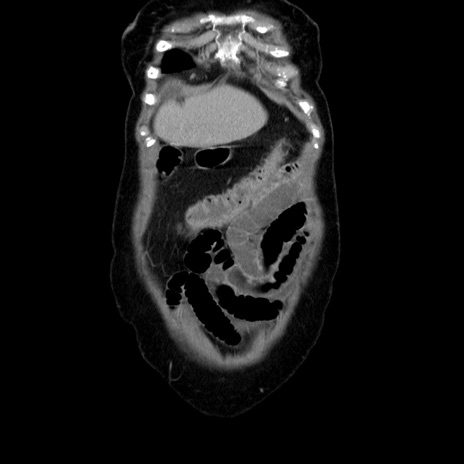

横断像

【症例】70歳代女性

【主訴】お腹が張る

【現病歴】1週間くらい前から腹部膨満の自覚あり。昨日夜から増悪したため、本日救急外来受診。

【身体所見】意識清明、BT 36.5℃、BP 165/106mmHg、HR 80bpm、SpO2 98%、腹部:膨満、軟、自発痛・圧痛なし、触診にて不快感あり、腸蠕動音:減弱

【データ】WBC 12600、CRP 1.04